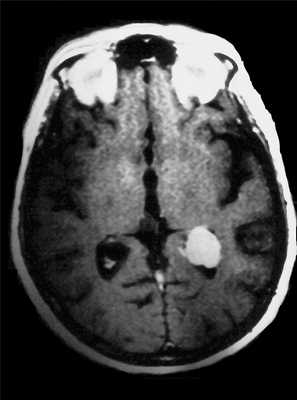

(а) Бесконтрастная КТ, аксиальный срез: у мужчины 33 лет с длительным анамнезом судорожных приступов в верхне-задней части правой теменной доли визуализируется кальцифицированное объемное образование, повторяющее ход извилин.

(б) MPT, FLAIR, аксиальный срез: у того же пациента в структуре коры визуализируется гипоинтенсивное объемное образование.